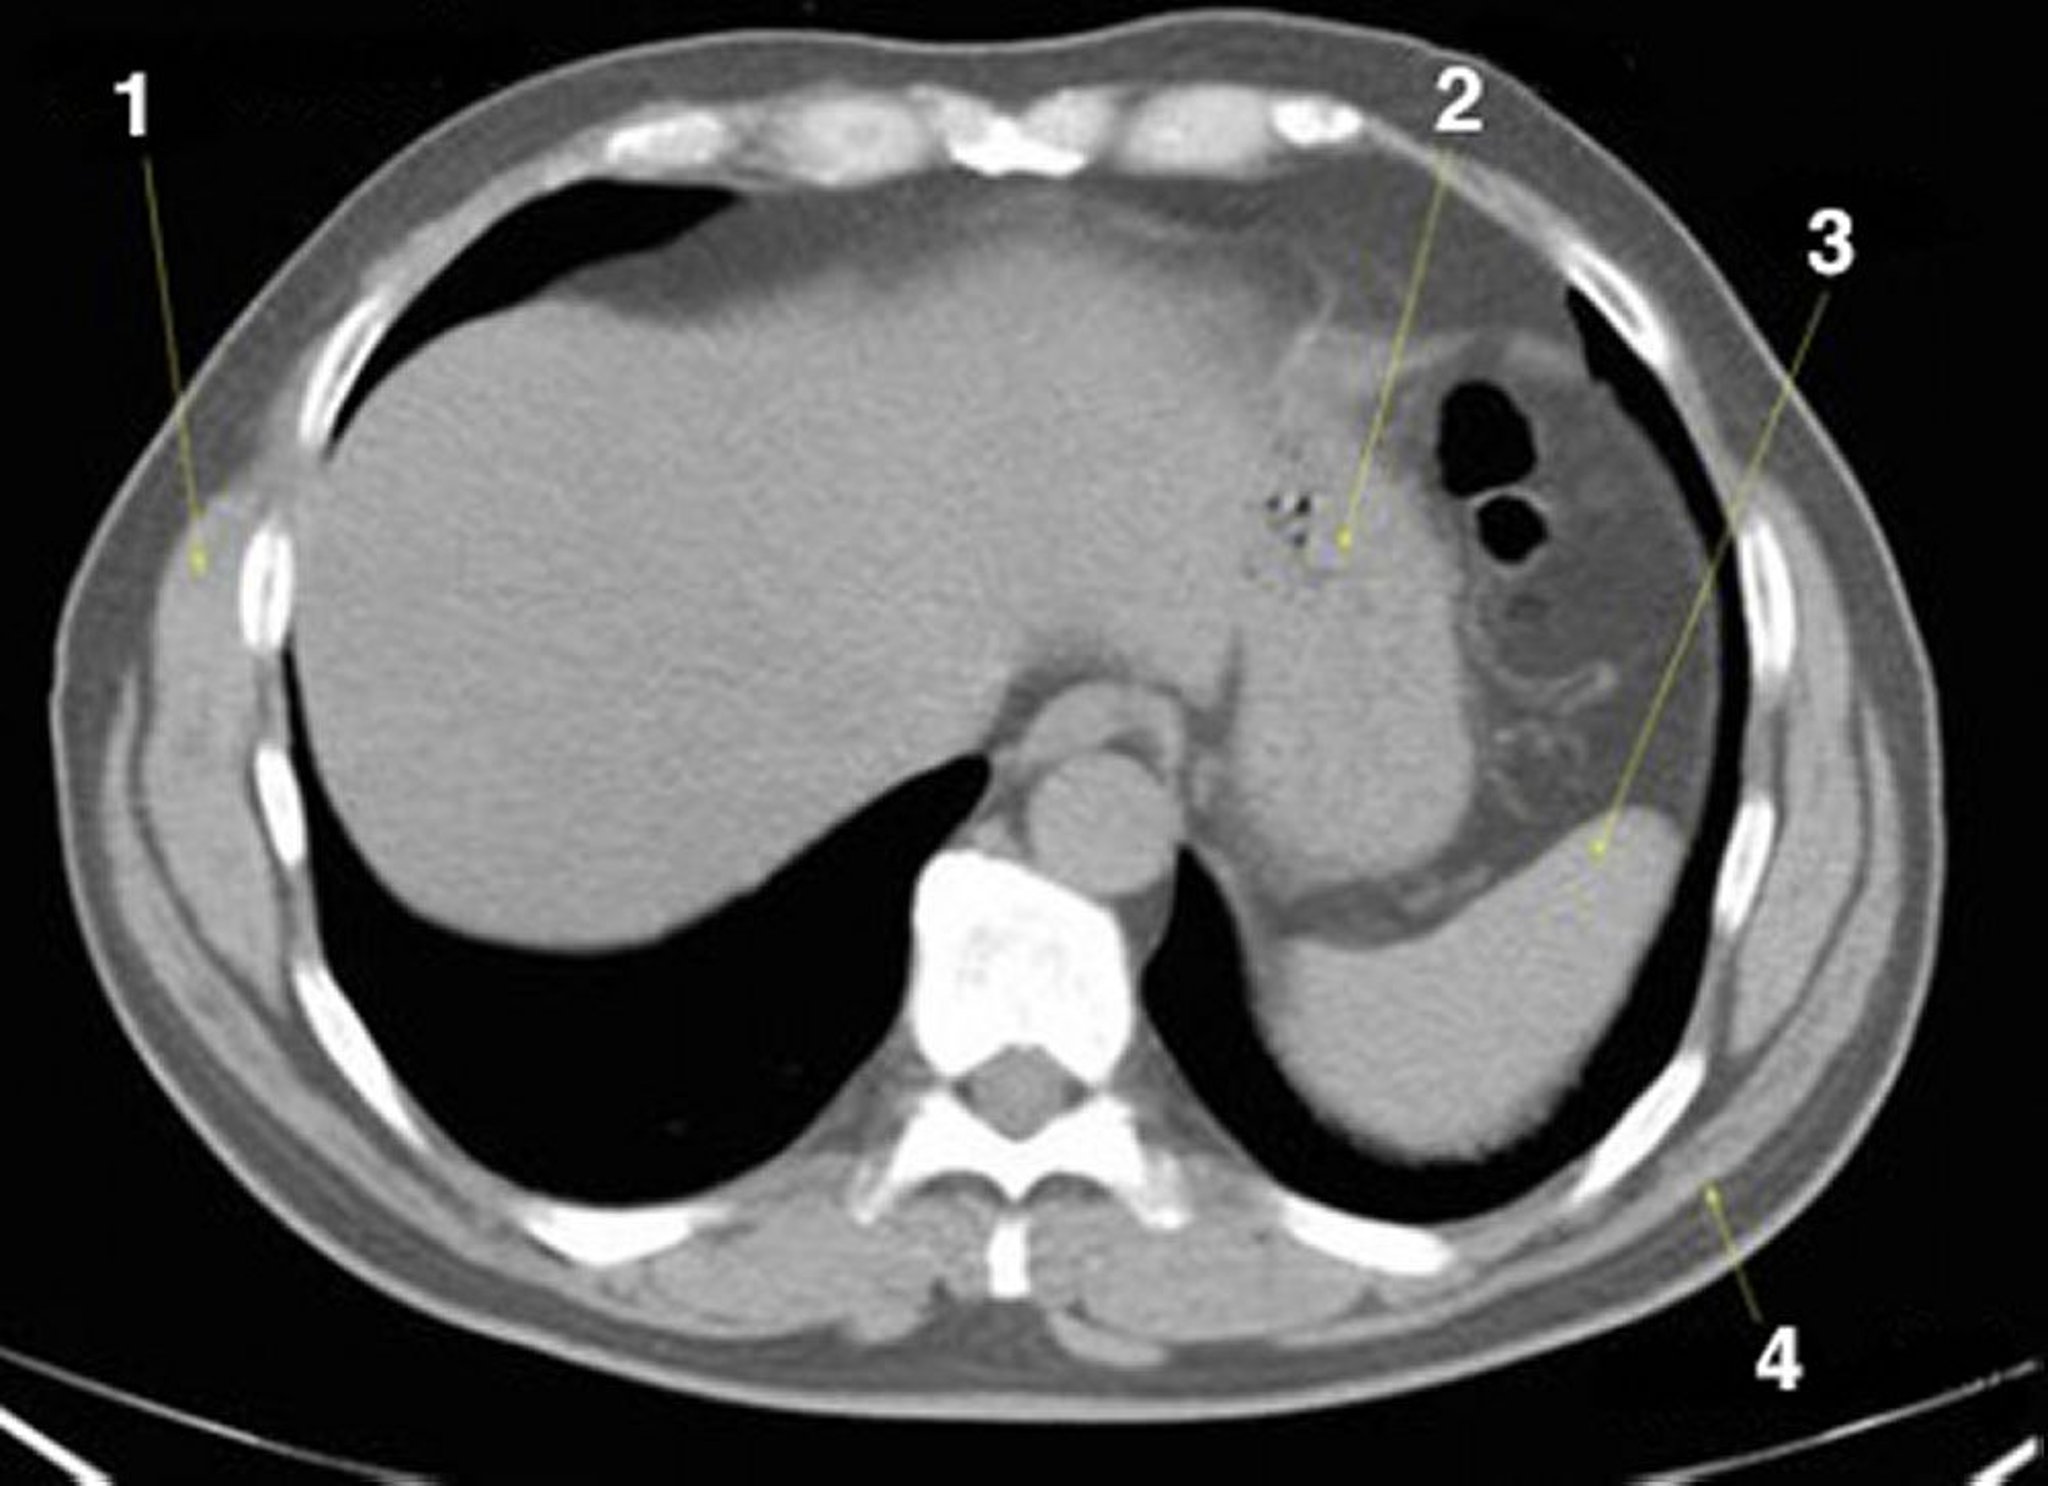

TDM sans contraste de l'abdomen et du bassin montrant une anatomie normale (diapositive 2)

1 = serratus anterior; 2 = estomac; 3 = rate; 4 = latissimus dorsi.